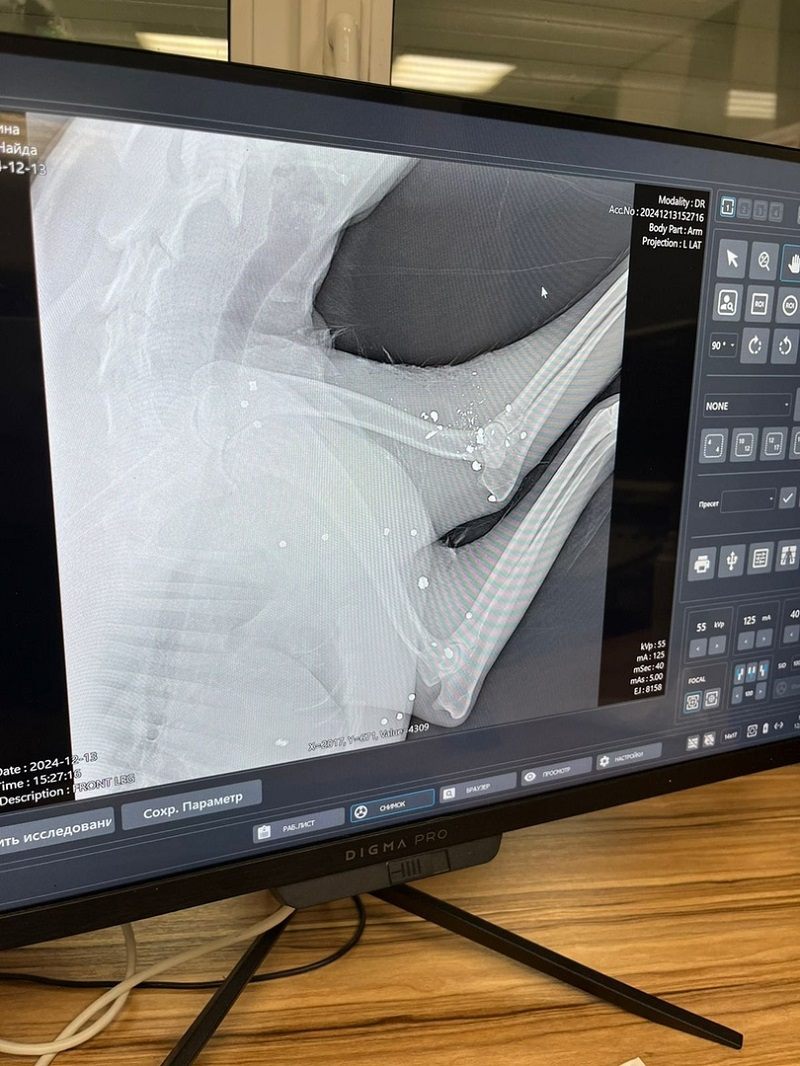

Получила продолжение история о собаке, которую неизвестный живодер буквально расстрелял на дороге в районе села Троекуровка. Несмотря на испытание, которая ей уготовила судьба, собака выжила, и те, кто сейчас занимается ее спасением, не опускают рук - борются за жизнь четвероногого друга. В Найду вошло более 30 пуль, одна из которых находится в очень опасном месте - в кармане сердца. И семье, выхаживающей несчастное животное, стоило усилий найти хирурга, который возьмется её оперировать. Однако, согласившийся ветеринар нашелся в Самаре, и на 9 января Найде назначена операция.